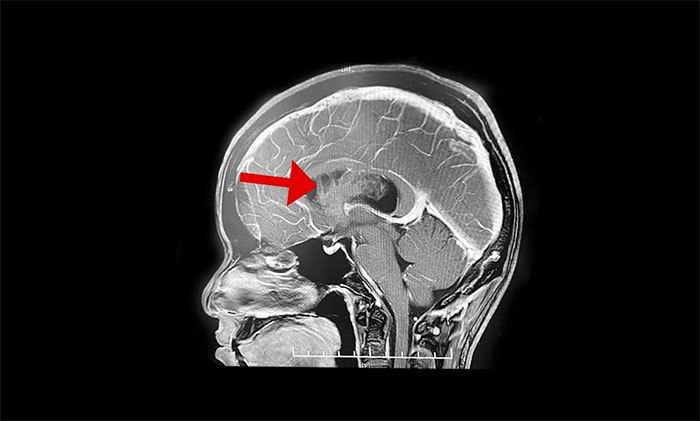

李士其教授介绍,该肿瘤一般生长于侧脑室或三脑室,由于生长的位置处于脑室内,有较大空隙代偿,疾病初期症状并不典型,当出现如头痛、呕吐等临床症状时,瘤体已经比较大。在治疗上首先建议进行手术切除,解除肿瘤占位效应,通畅脑脊液通路,缓解脑积水,解除颅内高压。李士其教授指出,中枢神经细胞瘤一般为偏良性肿瘤,若能手术全切肿瘤,或者大部分切除后辅助放疗可以长期生存。所以,手术这一步非常关键。

但由于肿瘤较大、血供丰富,且与脑室壁黏连明显,致使肿瘤分离及切除异常困难。而且脑室内血管及神经组织结构复杂、功能重要,如何在切除肿瘤的同时尽可能保护脑功能是手术的最大难点。